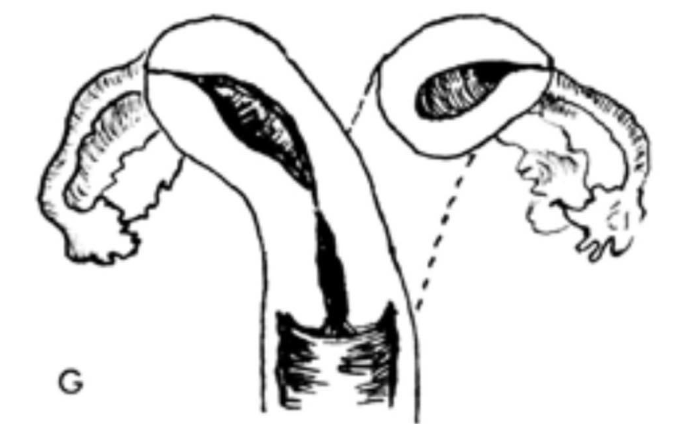

– Double vaginas, cervixes, and uteri function separately

– The two uteri are at approximately a 450 angle to one another

Uterus Didelphus

– Improper fusion leads to two partially or completely separate bicornuate uterine cavities.

– The uterus is heart-shaped

– Most common congenital uterine anomaly.

Bicornuate uterus

This is?

Bicornuate Uterus

– Two partially or completely separate endometrium form.

– The uterus is normally shaped

– Most common congenital uterine anomaly causing infertility.

Septate Uterus